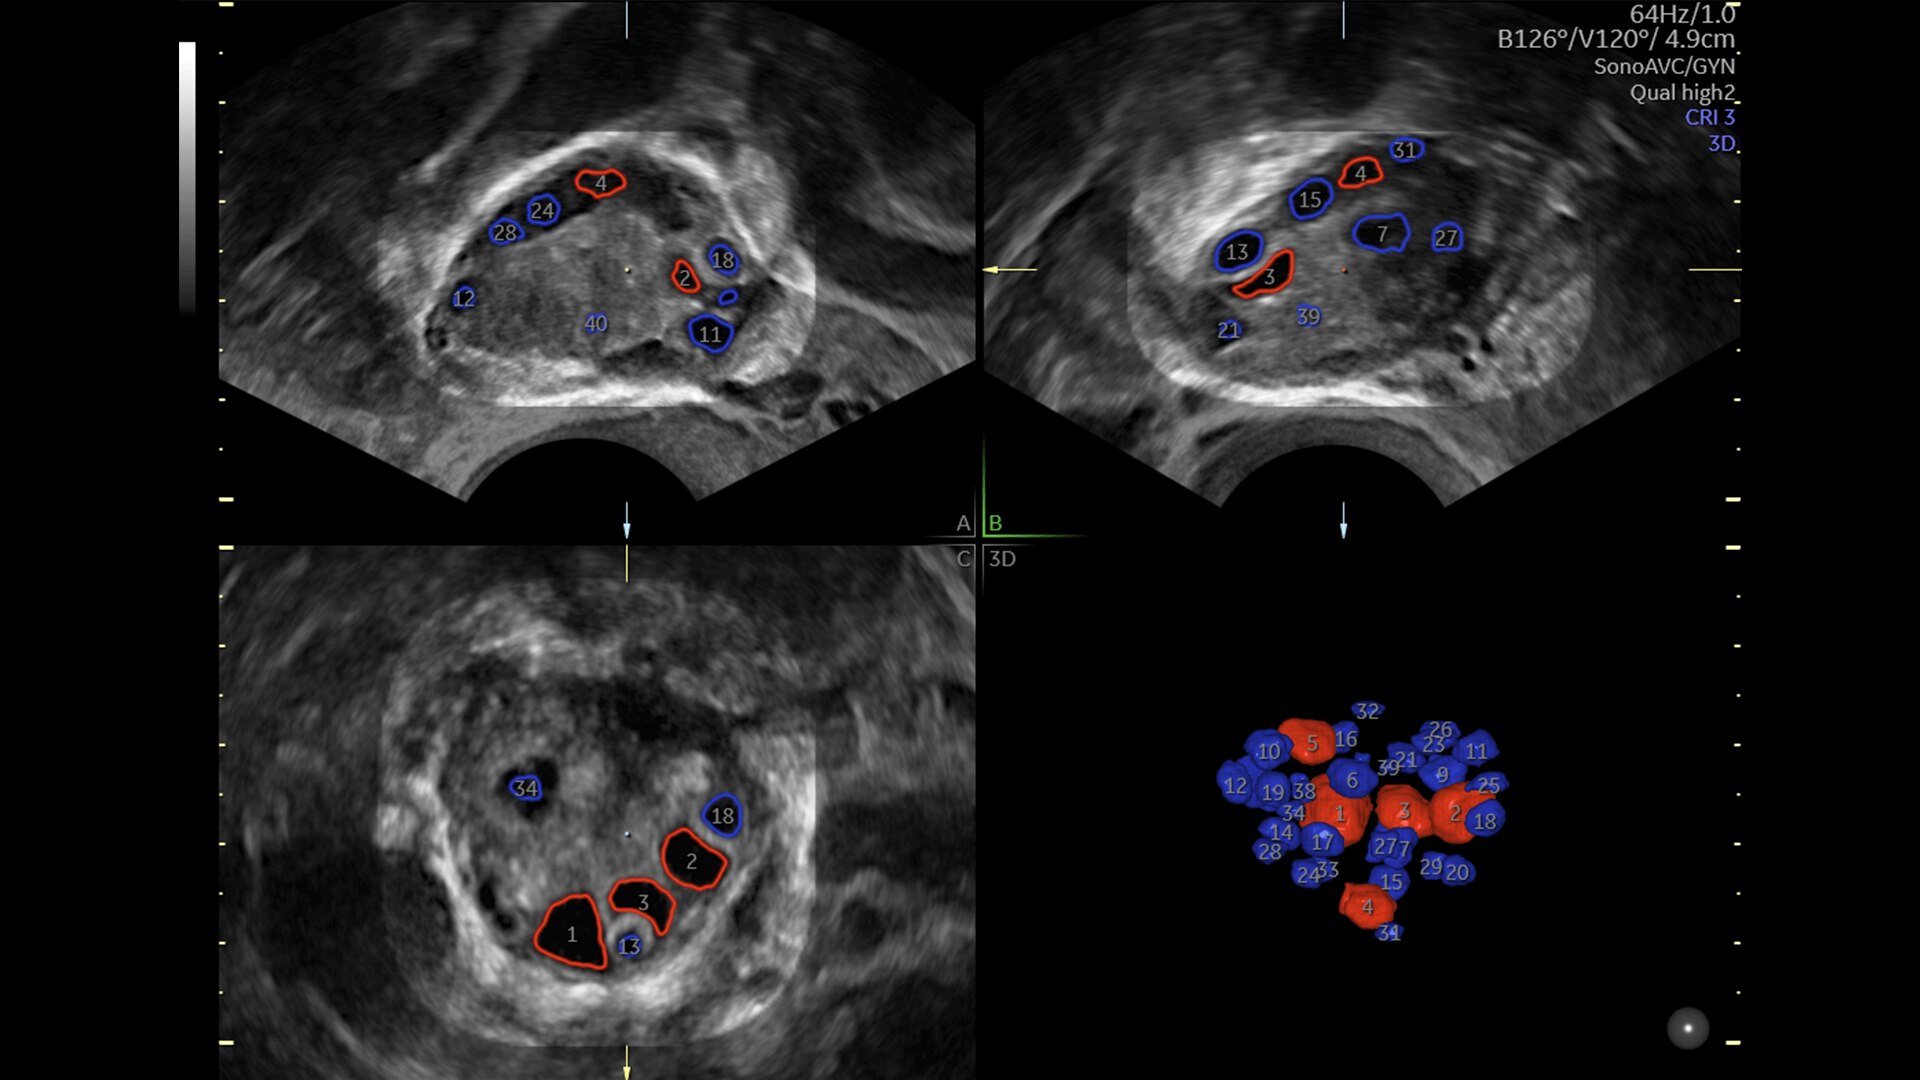

Pelvic Health

Offer patient answers faster with Ai-based automation tools